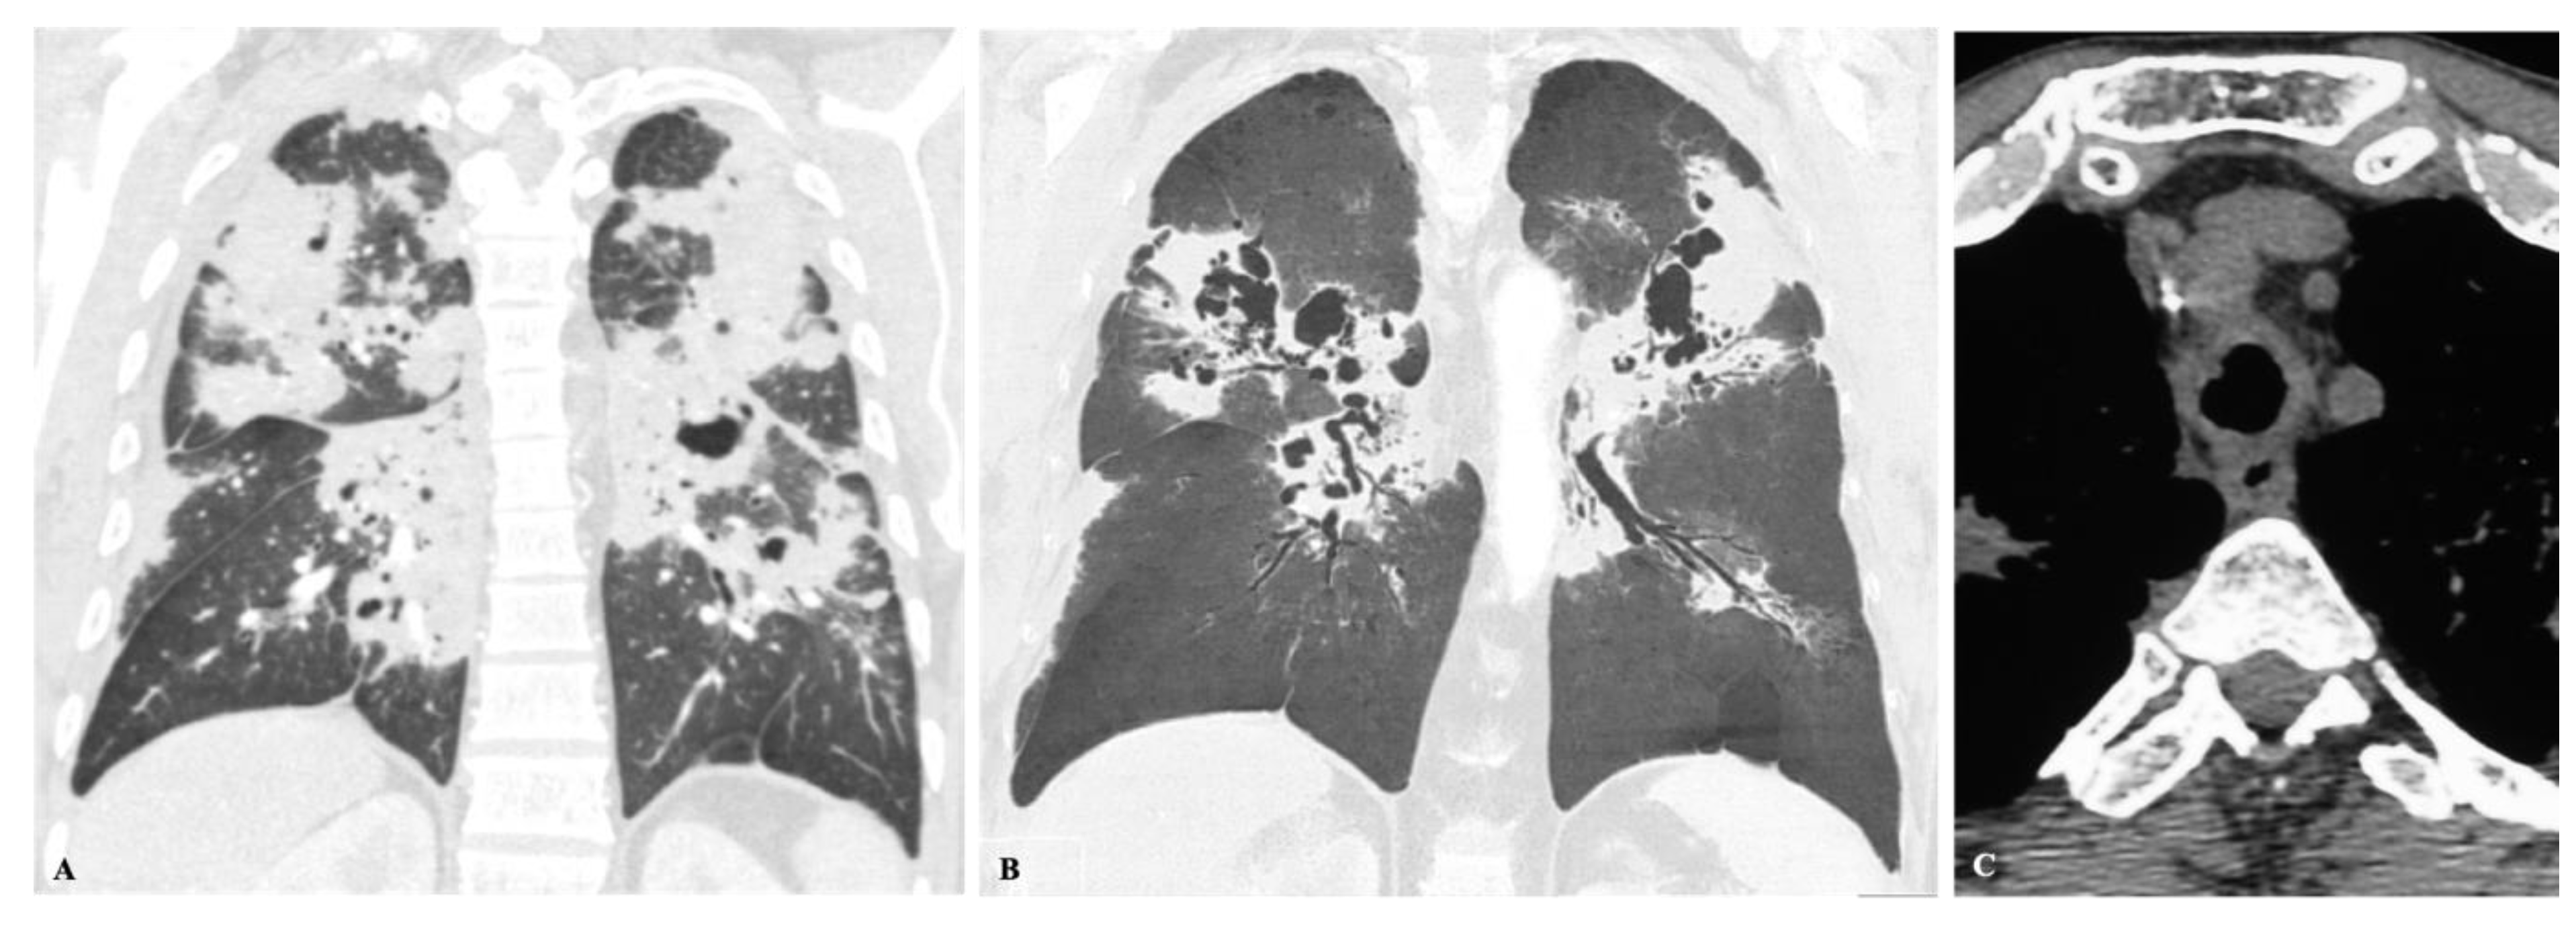

2.4. Disseminated Infection

- Wheat, L.J.; Connolly-Stringfield, P.A.; Baker, R.L.; Curfman, M.F.; Eads, M.E.; Israel, K.S.; Norris, S.A.; Webb, D.H.; Zeckel, M.L. Disseminated histoplasmosis in the acquired immune deficiency syndrome: Clinical findings, diagnosis and treatment, and review of the literature. Medicine (Baltimore) 1990, 69, 361–374. [Google Scholar] [CrossRef]

- Barreto, M.M.; Marchiori, E.; Amorim, V.B.; Zanetti, G.; Takayassu, T.C.; Escuissato, D.L.; Souza, A.S.; Rodrigues, R.S. Thoracic paracoccidioidomycosis: Radiographic and CT findings [published correction appears in Radiographics. Radiographics 2012, 32, 71–84. [Google Scholar] [CrossRef] [PubMed]